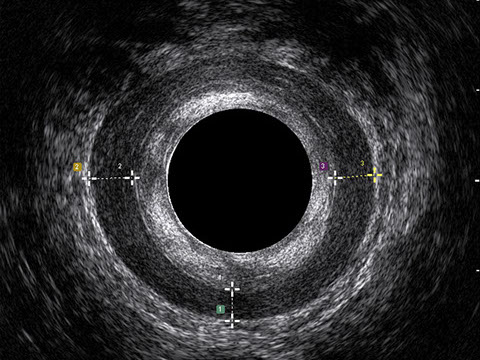

L’ecografia transanale è un esame diagnostico per immagini che consiste nell’introduzione di un trasduttore ad ultrasuoni. Le immagini qualitativamente migliori del canale anale sono ottenute usando un trasduttore rotante, montato in un manipolo rigido, che fornisce un’immagine a 360°. Con le apparecchiature più moderne è anche possibile ottenere immagini tridimensionali.

L’ecografia transanale permette di distinguere la sottomucosa che riveste il canale anale, lo sfintere anale interno, e lo sfintere anale esterno.